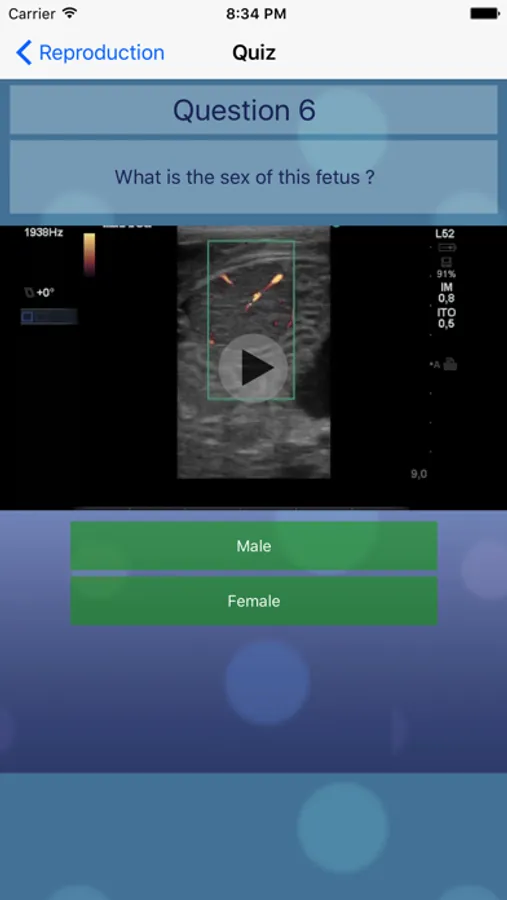

•Fetal sexing

Comprehensive notes are included for each condition with multiple still images. Fetal sexing is described and carefully illustrated in multiple planes for each stage of gestation. The still pictures demonstrate the classic appearance of each stage and are labeled where necessary. The video loops simulate the real life situation and allow the user to test their observational skills on moving images. This is an invaluable tool for continuing professional education of any veterinarian interested in stud work.